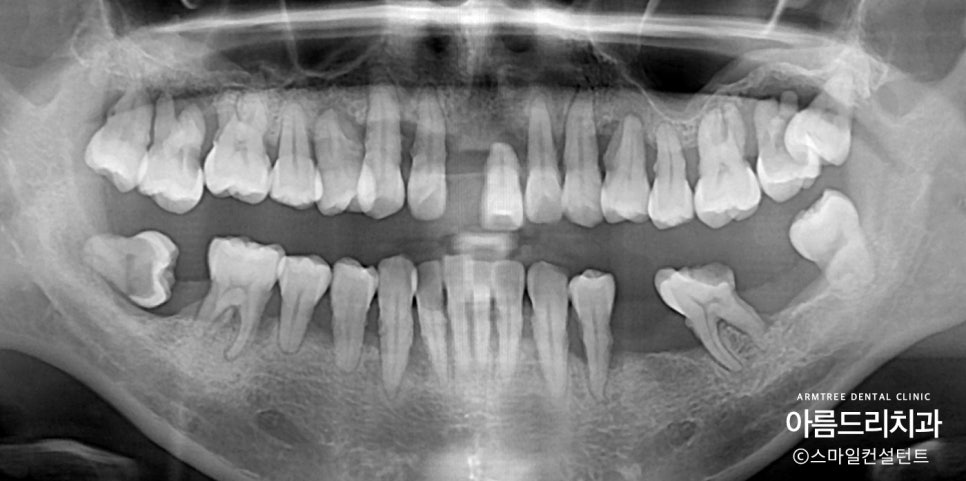

딱 봐도 전체적으로 잇몸이 좋지 않습니다.

사실상 살릴만한 치아가 거의 없네요.

치아가 중간중간 없기 때문에

교합이 무너지면서 좌우 위아래

전부 밸런스가 무너져 있습니다.

나이가 젊은 환자분이시기에

전부다 발치하고 임플란트 심는 것이

마음이 아팠습니다.

우선 가망성이 아예 없는

위 앞니와 사랑니들은 발치했습니다.

그리고 잇몸치료를 열심히 해서

나머지 치아들은 최대한 유지했습니다.

그리고 무너지 밸런스를 잡기 위해

아래 치아들만 짧게 교정을 진행했습니다.